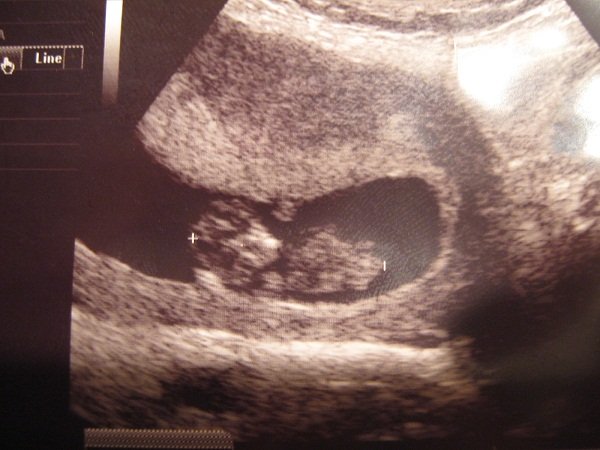

Nagyon jó volt az Istenhegyin, pikk-pakk levették a vért, aztán nem egészen egy óra múlva megvolt az uh, rettenetesen alapos volt a doki, 6-szor is megmérte a tarkóredőt (mert a határ határán volt, 2.4, és 2.5 felett szokott rezegni a léc, 3 felett rossz), aztán jól megnéztük mindenét, még 4D-ben is (sose voltam ilyenen:D), mindent elmagyarázott, végül kaptam egy dvd-t, és jó véreredményt kívánt.

– Akkor merek tippelni, mert nem fog haragudni, ha mégis tévedek. Szerintem kisfiú, és az ott egy kuki